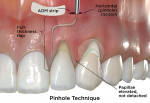

Pinhole Technique

Developed by Chao in 2012, the pinhole technique is the newest of the minimally invasive CAF techniques described for recession coverage.27 The technique involves a 2 mm to 3 mm mucosal horizontal incision (termed a "pinhole" incision) near the base of the vestibule, apical to the teeth that are planned for recession coverage (Fig 5 e, Pinhole Technique). Specialized instruments are inserted through the incision to mobilize a full-thickness flap, which is extended to undermine interdental papillae two teeth mesial and distal to the recession area. Next, small graft strips are inserted through the pinhole incision and packed into place within the subgingival spaces and underneath papillae and marginal soft tissue. No sutures are required, but firm digital pressure is recommended for 5 minutes following material placement. Lastly, the pinhole incision is left to heal by first intention without suturing.

This technique can be used for Miller class I, class II, and class III multiple adjacent gingival recession defects, including in the esthetic zone.27,28 Because this technique is relatively newly developed, however, a minimal amount of supporting evidence for it exists in the literature.

To summarize, the pinhole technique's advantages are the lack of a need for sutures, good esthetic results, minimal postoperative morbidity, and quick healing.27,28 On the downside, specialized instruments are required, a learning curve is necessary, and results in the mandible typically are not as good as in the maxilla as certain factors favor the maxillary arch compared with the mandible, such as the width of keratinized tissue and favorable shape of the papillary tissue.27,28